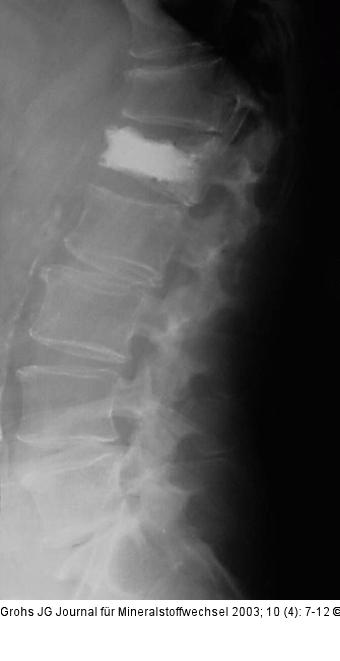

Abbildung 7: Ballon-Kyphoplastik Wirbelkörper L1 aus Abb. 1 nach Aufrichtung und Stabilisierung mittels Ballon-Kyphoplastik. |

Wirbelkörper L1 aus Abb. 1 nach Aufrichtung und Stabilisierung mittels Ballon-Kyphoplastik. |